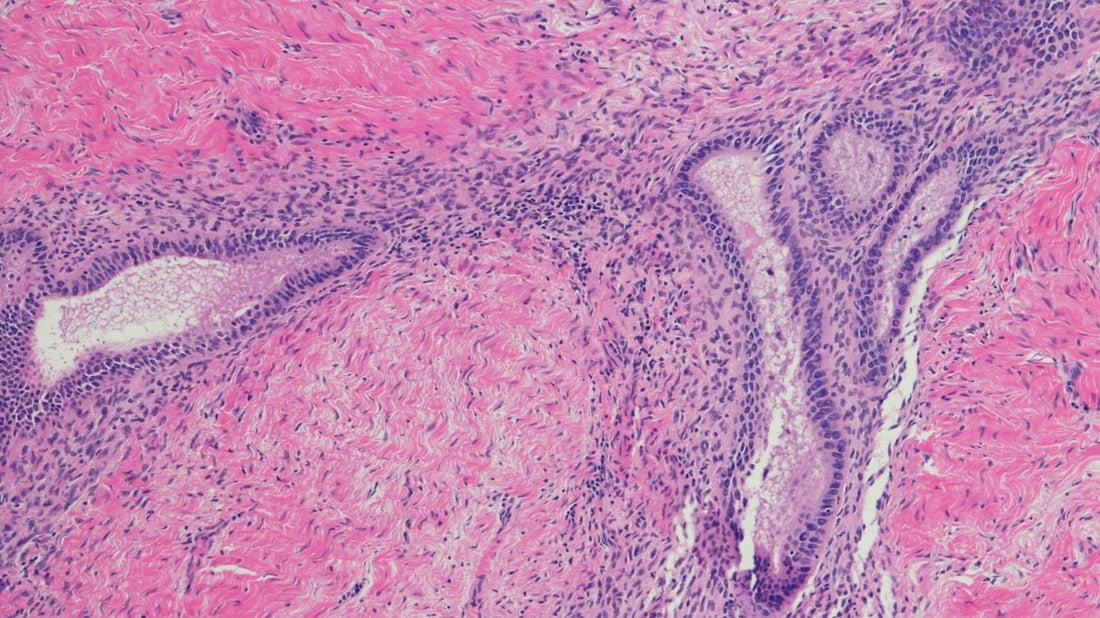

Qu’est ce que l’endométriose ? L’endométriose est une maladie inflammatoire chronique qui touche environ 1 femme sur 10 en âge de procréer. Elle se caractérise par la présence anormale de tissu endométrial (endomètre) en dehors de l’utérus (ovaires, trompes, vessie, intestin..) Sous l’influence des hormones, ces tissus réagissent comme la muqueuse utérine normale, ils s’épaississent, saignent mais ne peuvent pas s’évacuer ce qui entraîne une inflammation chronique, des douleurs, des adhérences et parfois une infertilité. Quels sont les signes de l'endométriose ? Les symptômes les plus fréquents sont des règles très douloureuses, des douleurs pelviennes chroniques( même en dehors des règles), des douleurs lors des rapports sexuels, des troubles digestifs ou urinaires, une fatigue chronique, des difficultés à concevoir un enfant. Quelles sont les causes de l’endométriose ? La cause exacte n’est pas encore connue mais plusieurs facteurs semblent impliqués : génétique immunité facteurs environnementaux Il n’existe pas à ce jour de traitement curatif définitif mais plusieurs approches permettent de soulager les symptômes et préserver la fertilité comme : les traitements hormonaux la chirurgie dans les cas les plus sévères l’approche complémentaires et naturelles elle va permettre la réduction de l’inflammation notamment via le zinc et de la vitamine D la gestion de stress grâce au magnésium

Comment définit-on une bonne qualité ovocytaire ? La qualité ovocytaire désigne la capacité d’un ovocyte (ou ovule) à être fécondé, à se diviser correctement et à donner un embryon viable. C’est l’un des facteurs clés de la fertilité féminine au même titre que l’ovulation ou la réserve ovarienne. Un ovocyte de bonne qualité possède un matériel génétique intègre, une bonne fonction mitochondriale, un équilibre oxydatif optimal ce qui lui confère la capacité de développer en embryon sain. La qualité ovocytaire dépend de plusieurs paramètres : l’âge : → La qualité ovocytaire diminue progressivement à partir de 35 ans. le stress oxydatif : → Les radicaux libres endommagent l’ADN ovocytaire. l’état inflammatoire chronique : → La présence de pathologie comme l’endométriose, le SOPK.. les troubles métaboliques : → L’insulinorésistance (SOPK), les carences nutritionnelles. l’environnement → L’exposition à des perturbateurs endocriniens, la pollution, la consommation de tabac, d’alcool, de drogues.. → La qualité du sommeil, du microbiote intestinal et la gestion du stress. On ne peut pas créer de nouveaux ovocytes mais on peut améliorer leur développement pendant les 3 mois qui précèdent l’ovulation. C’est durant cette phase de maturation folliculaire que les ovocytes sont les plus sensibles aux apports nutritionnels, hormonaux et environnementaux. Comment peut-on améliorer la qualité ovocytaire ? Pour soutenir la qualité ovocytaires il existe plusieurs solutions : une supplémentation en myo-inositol (pour l’équilibre hormonal), en Folates (avec de la vitamine B9 active!), en vitamine B12, en Zinc, en iode, en vitamine D et en antioxydants (telle que la vitamine E ou la vitamine C) la gestion du stress un sommeil réparateur une activité physique douce (yoga, pilates, marche, natation… ) une réduction de l’exposition aux toxiques (tabac, alcool, drogues…)